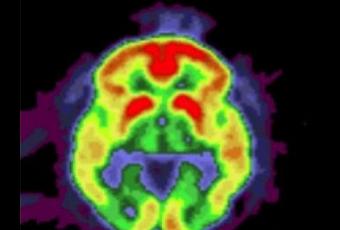

Sources: PLoS One, Feb. 1, 2012 doi:10.1371/journal.pone.0031039Rare variants in APP, PSEN1 and PSEN2 increase risk for AD in late-onset Alzheimer's disease families.et Washington University School of Medicine(Visuel Knight Alzheimer's Disease Research Center: L'image du cerveau montre une accumulation de dépôts amyloïdes (jaune et rouge) chez un patient ayant la maladie d'Alzheimer).